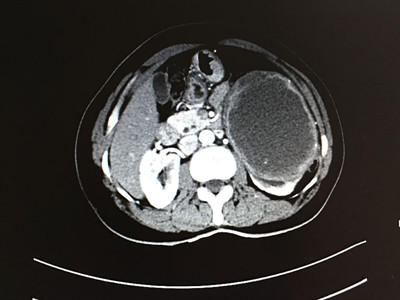

两位患者均为体检时发现后腹腔有一巨大占位,进行详细检查发现肿瘤。据患者介绍,平常并无特别明显症状。其中一名患者为右肾错构瘤,属血管平滑肌脂肪瘤,长25公分,宽16公分,厚13公分,与肝脏、肾动静脉和腔静脉粘连紧密,并将腔静脉挤弯变形、推向左侧。和右肾连在一起有半个足球大小。另一名患者为左肾透明细胞癌,直径21公分左右,囊实性占位病变,与胰腺粘连紧密,肾血管受挤压位置变异。